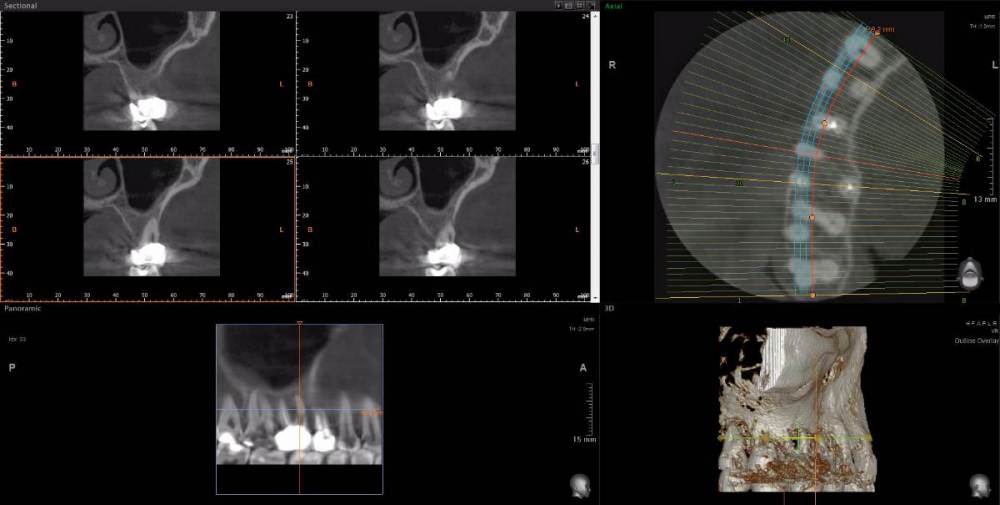

Рабин Опубликовано 18 мая, 2021 Автор Поделиться Опубликовано 18 мая, 2021 Добрый день! Сделала КТ этого зуба, как вы просили... https://cloud.mail.ru/stock/kkbze24nzBzfEqnUbdPwtsei Видите ли вы воспаление на нём и можно ли его спасти? Интересует также соседний 15 зуб. Спасибо! Ссылка на комментарий

wladdX Опубликовано 18 мая, 2021 Поделиться Опубликовано 18 мая, 2021 (изменено) Зуб 16, на мой взгляд, придётся удалить. Зуб 18 тоже Зуб 15 вроде бы и не вызывает особых восторгов, но и явного неприятия тоже. Изменено 18 мая, 2021 пользователем wladdX 2 Ссылка на комментарий

red_butler Опубликовано 20 мая, 2021 Поделиться Опубликовано 20 мая, 2021 18.05.2021 в 23:24, wladdX сказал: Зуб 16, на мой взгляд, придётся удалить. +1 Ссылка на комментарий

wladdX Опубликовано 29 мая, 2021 Поделиться Опубликовано 29 мая, 2021 18 - там приличных размеров корневая гранулёма, излечить нереально 1 Ссылка на комментарий